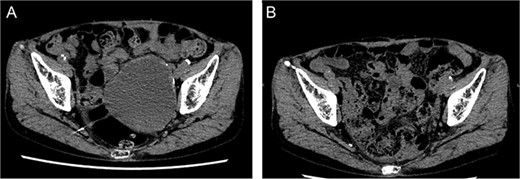

He underwent surgery under general anesthesia. A midline abdominal incision and an intraperitoneal approach were employed. Due to the aneurysm’s size, combined with adhesions to the surrounding intestines and the thinness of the aneurysm wall, achieving complete exposure was particularly challenging. Therefore, the aneurysm was incised midway. The hematoma and coils were removed, and the feeding vessels were ligated with 3–0 monofilament. Blood oozing from the feeding vessels suggested that the aneurysm expansion was likely due to a type II endoleak that was not visible on contrast-enhanced CT. The laparoscope was used to observe the aneurysm, identify, and ligate the inflow vessels that were difficult to visualize directly (Fig. 2). The IIA was sutured with 3–0 monofilament using laparoscopic assistance, taking care to avoid including adjacent structures such as the rectum in the sutures. The operation took 255 min, and the patient was discharged on the fourteenth day postoperation. Follow-up CT at 10 months postoperation showed a reduction in aneurysm size (Fig. 3).

Postoperative computed tomography showing a reduction in aneurysm size. A—Preoperative image, B—10-month postoperative image.